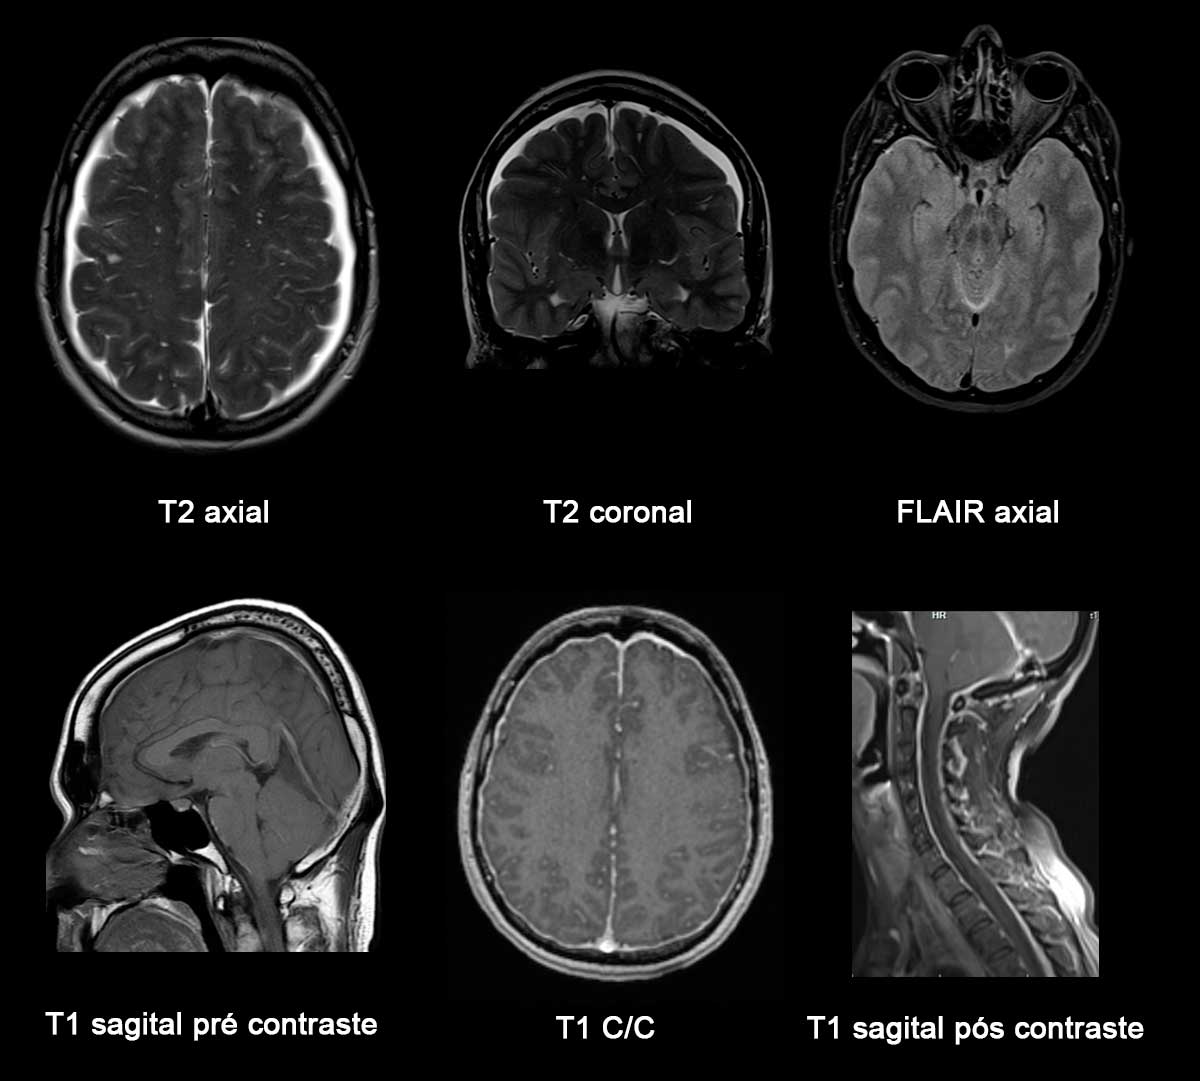

cefaleia facadacefaleia PDF)cefaleia Headachecefaleia precipitatedcefaleia bycefaleia Valsalvacefaleia maneuverscefaleia incefaleia patientscefaleia withcefaleia cefaleia congenitalcefaleia Chiaricefaleia Icefaleia malformationcefaleia Grátis:cefaleia SuperMaterialSanarflixcefaleia -